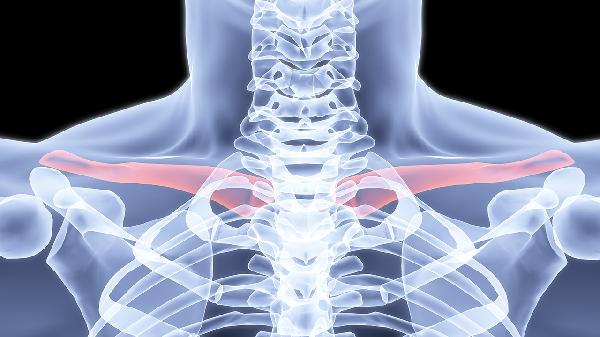

锁骨骨折可能出现后遗症,常见的有肩关节活动受限和骨不连。锁骨骨折多由外伤导致,骨折后若未规范治疗或康复不当,可能引发后遗症,建议患者及时就医并遵医嘱进行康复训练。

锁骨骨折后若固定不牢固或过早活动,可能影响骨折愈合,导致骨不连。骨不连表现为局部持续疼痛、异常活动,X线检查可见骨折线清晰无愈合迹象。此时需手术清除纤维组织并重新固定,配合植骨促进愈合。术后需严格制动,避免二次损伤。

部分患者因长期制动或康复训练不足,可能出现肩关节活动受限。表现为外展、上举困难,伴随肌肉萎缩。需通过渐进式功能锻炼恢复,如钟摆运动、爬墙训练等。严重者需在康复师指导下使用器械辅助,避免强行活动加重损伤。